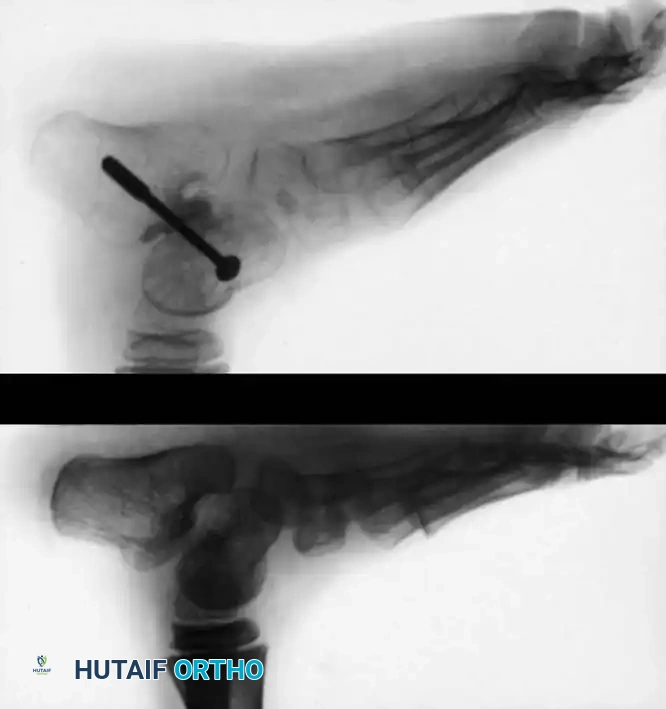

Open Reduction and Extraarticular Subtalar Fusion (Grice-Green)

For older children (4 to 8 years) presenting with severe, neglected, or recurrent CVT, soft-tissue realignment alone is insufficient due to adaptive bony changes. Coleman et al. popularized combining the open reduction technique with a Grice-Green extraarticular subtalar arthrodesis to provide a permanent osseous block to talar plantarflexion.

Surgical Technique:

1. Exposure: Make a short curvilinear incision over the lateral aspect of the foot, directly overlying the sinus tarsi.

2. Preparation of the Sinus Tarsi: Incise the cruciate ligament in the direction of its fibers. Evacuate the fat pad and ligamentous debris from the sinus tarsi. Reflect the extensor digitorum brevis distally.

3. Hindfoot Reduction: Place the foot in equinus and invert it to mechanically lever the calcaneus directly beneath the talus, correcting the valgus and equinus deformity. In severe cases, a posterior subtalar capsulotomy or limited lateral calcaneal ostectomy may be required to achieve reduction.

4. Graft Bed Preparation: Insert a broad periosteal elevator into the sinus tarsi to block the subtalar joint in its corrected position and determine the required graft dimensions. Prepare the recipient beds by decorticating a thin layer of cortical bone from the inferior surface of the talar neck and the superior surface of the anterior calcaneus.

- Graft Harvest and Insertion: Harvest a cortical bone block (typically 3.5 to 4.5 cm long and 1.5 cm wide). The anteromedial proximal tibial metaphysis is the traditional donor site, though a segment of the distal fibula or a tricortical iliac crest graft provides excellent structural support. Shape the graft with a rongeur to allow it to be countersunk into the cancellous beds, preventing lateral extrusion.

- Fixation: With the foot held in slight overcorrection, impact the graft into the sinus tarsi. Evert the foot slightly to lock the graft under compression.

Surgical Pearl (Dennyson and Fulford Modification): To prevent graft dislodgement and increase fusion rates, utilize rigid internal fixation. Pass a cancellous screw anteriorly from the dorsal talar neck, through the graft, and into the body of the calcaneus.

- Equinus Correction: Once the subtalar joint is stabilized by the graft, assess ankle dorsiflexion. Perform a percutaneous or open Achilles tendon lengthening to correct residual ankle equinus.

- Immobilization: Apply a long leg cast with the knee flexed, the ankle in maximal safe dorsiflexion, and the hindfoot in neutral.